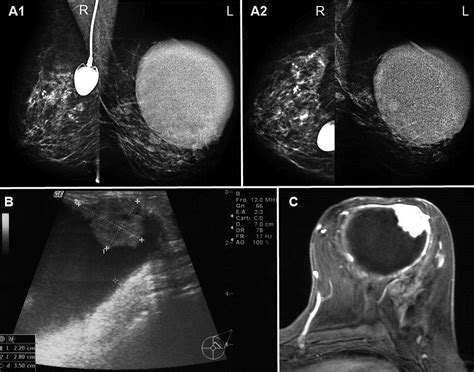

Mammography Screening or diagnostic imaging to visualize the internal structure of the breast.

Breast Ultrasound High-resolution imaging used to evaluate lumps and look inside the ducts for abnormal growth.

Ductogram (Galactogram) A specialized test where contrast dye is injected into the affected duct to visualize the blockage or growth.